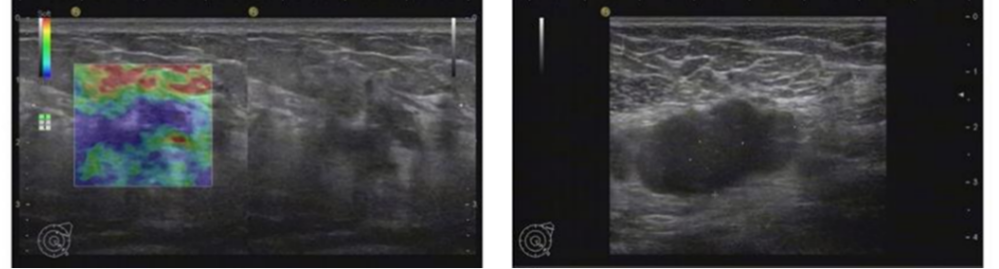

2021年6月颅脑增强MRI:左侧小脑占位,考虑转移瘤。

图2.颅脑增强MRI

2022年5月颅脑增强MRI:左侧小脑肿瘤切除术后改变。

疗效评价CR,继续维持曲妥珠单抗(汉曲优)+吡咯替尼+卡培他滨治疗方案

图3.颅脑增强MRI